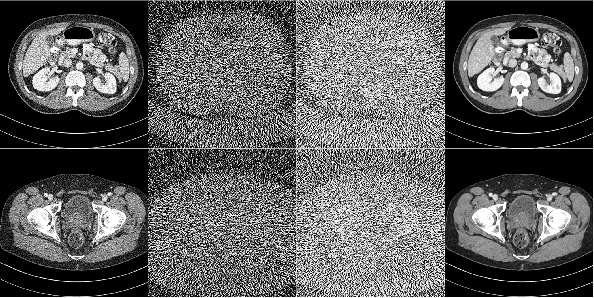

Abstract:Noise and artifacts are intrinsic to low dose CT (LDCT) data acquisition, and will significantly affect the imaging performance. Perfect noise removal and image restoration is intractable in the context of LDCT due to the statistical and technical uncertainties. In this paper, we apply the generative adversarial network (GAN) framework with a visual attention mechanism to deal with this problem in a data-driven/machine learning fashion. Our main idea is to inject visual attention knowledge into the learning process of GAN to provide a powerful prior of the noise distribution. By doing this, both the generator and discriminator networks are empowered with visual attention information so they will not only pay special attention to noisy regions and surrounding structures but also explicitly assess the local consistency of the recovered regions. Our experiments qualitatively and quantitatively demonstrate the effectiveness of the proposed method with clinic CT images.